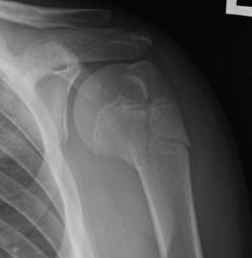

Case: 16 year old boy

Initial injury 18 months post injury